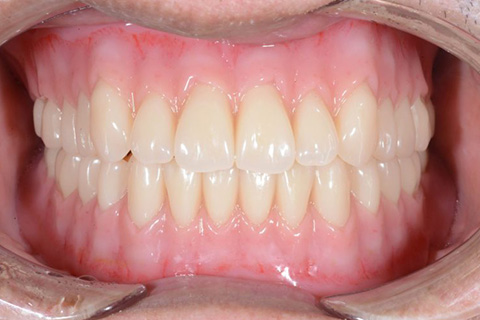

どこが入れ歯かわかりますか?

(このページの最後に正解があります)

入れ歯の一番の悩みとして『見た目が悪い』。中でも前歯のワイヤーが嫌な方が多くおられます。トップの歯の写真を見てください。奥歯に少し金属が見られますが、唇で隠れるところなので、患者様は全く気にならずに、お友達とお食事や会話を楽しんでおられます。

最後にこのページの一番初めにのっていた方の治療前の写真をのせておきます。治療前とは比べものにならないぐらい自然な入れ歯が入っていることがお分かりになられると思います。

トップの写真の治療前の状態